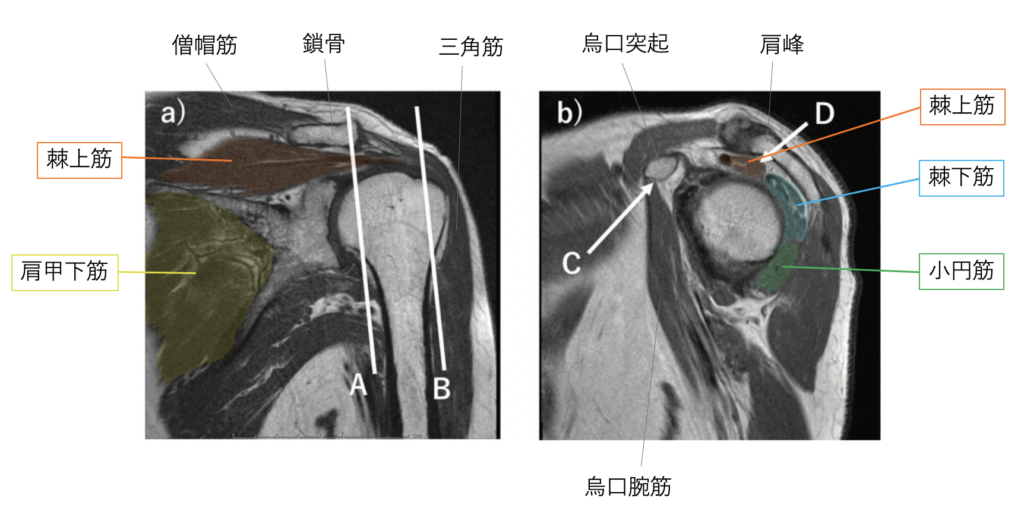

関節唇および肩甲上腕靱帯の正常変異とMRI画像所見のポイント。医療機関の方へ|御池クリニック。SLAP損傷 | ラドライフ。「関節のMRI」上谷 雅孝 / 青木 隆敏 / 神島 保定価: ¥ 13000#上谷雅孝 #上谷_雅孝 #青木隆敏 #青木_隆敏 #神島保 #神島_保 #本 #自然/医療・薬学・健康裁断済みのため全体的に状態が悪いとしております。口腔外科学 第4版 医歯薬出版 裁断済み。。医療機関の方へ|御池クリニック。素人裁断であることをご了承ください。また、本商品の他にも多数医学書を出品しておりますので、合わせてご検討ください。【koro】イラスト解剖学 改訂10版 最新版